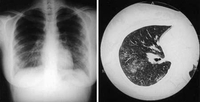

Pneumonia por Coxiella burnetii. Radiografia torácica e tomografia computadorizada (TC) de uma mulher de 21 anos de idade com pneumonia por Coxiella burnetii; a radiografia torácica exibe múltiplas áreas de condensação suave bilaterais nos campos pulmonares médios e inferiores; a tomografia computadorizada (TC) exibe nódulos centrolobulares pouco definidos e consolidação do espaço aéreo

Okimoto N, et al. Respirology. 2004;9:278-282; used with permission of John Wiley & Sons Ltd